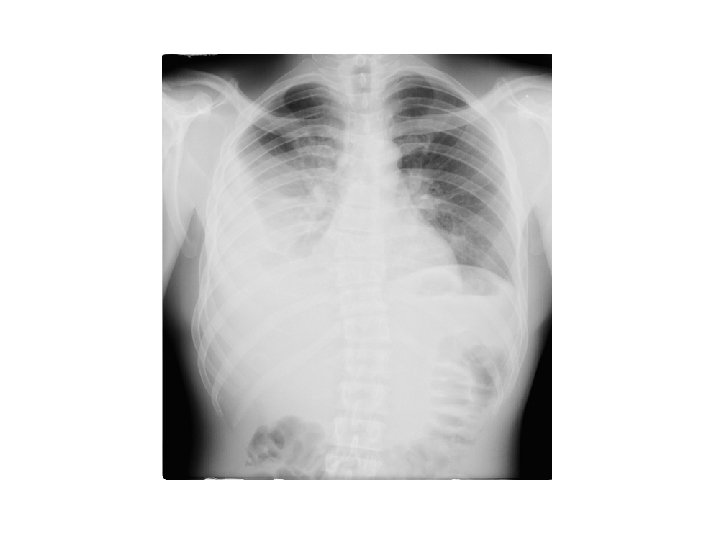

Cas clinique 2 • • • M O. , 55 ans, douleur thoracique droite, brutale, non fébrile tabagisme à 50 PA, sevré il y a 1 an diminution du murmure vésiculaire crépitement sous cutané

• Diagnostic ? • Traitement ?